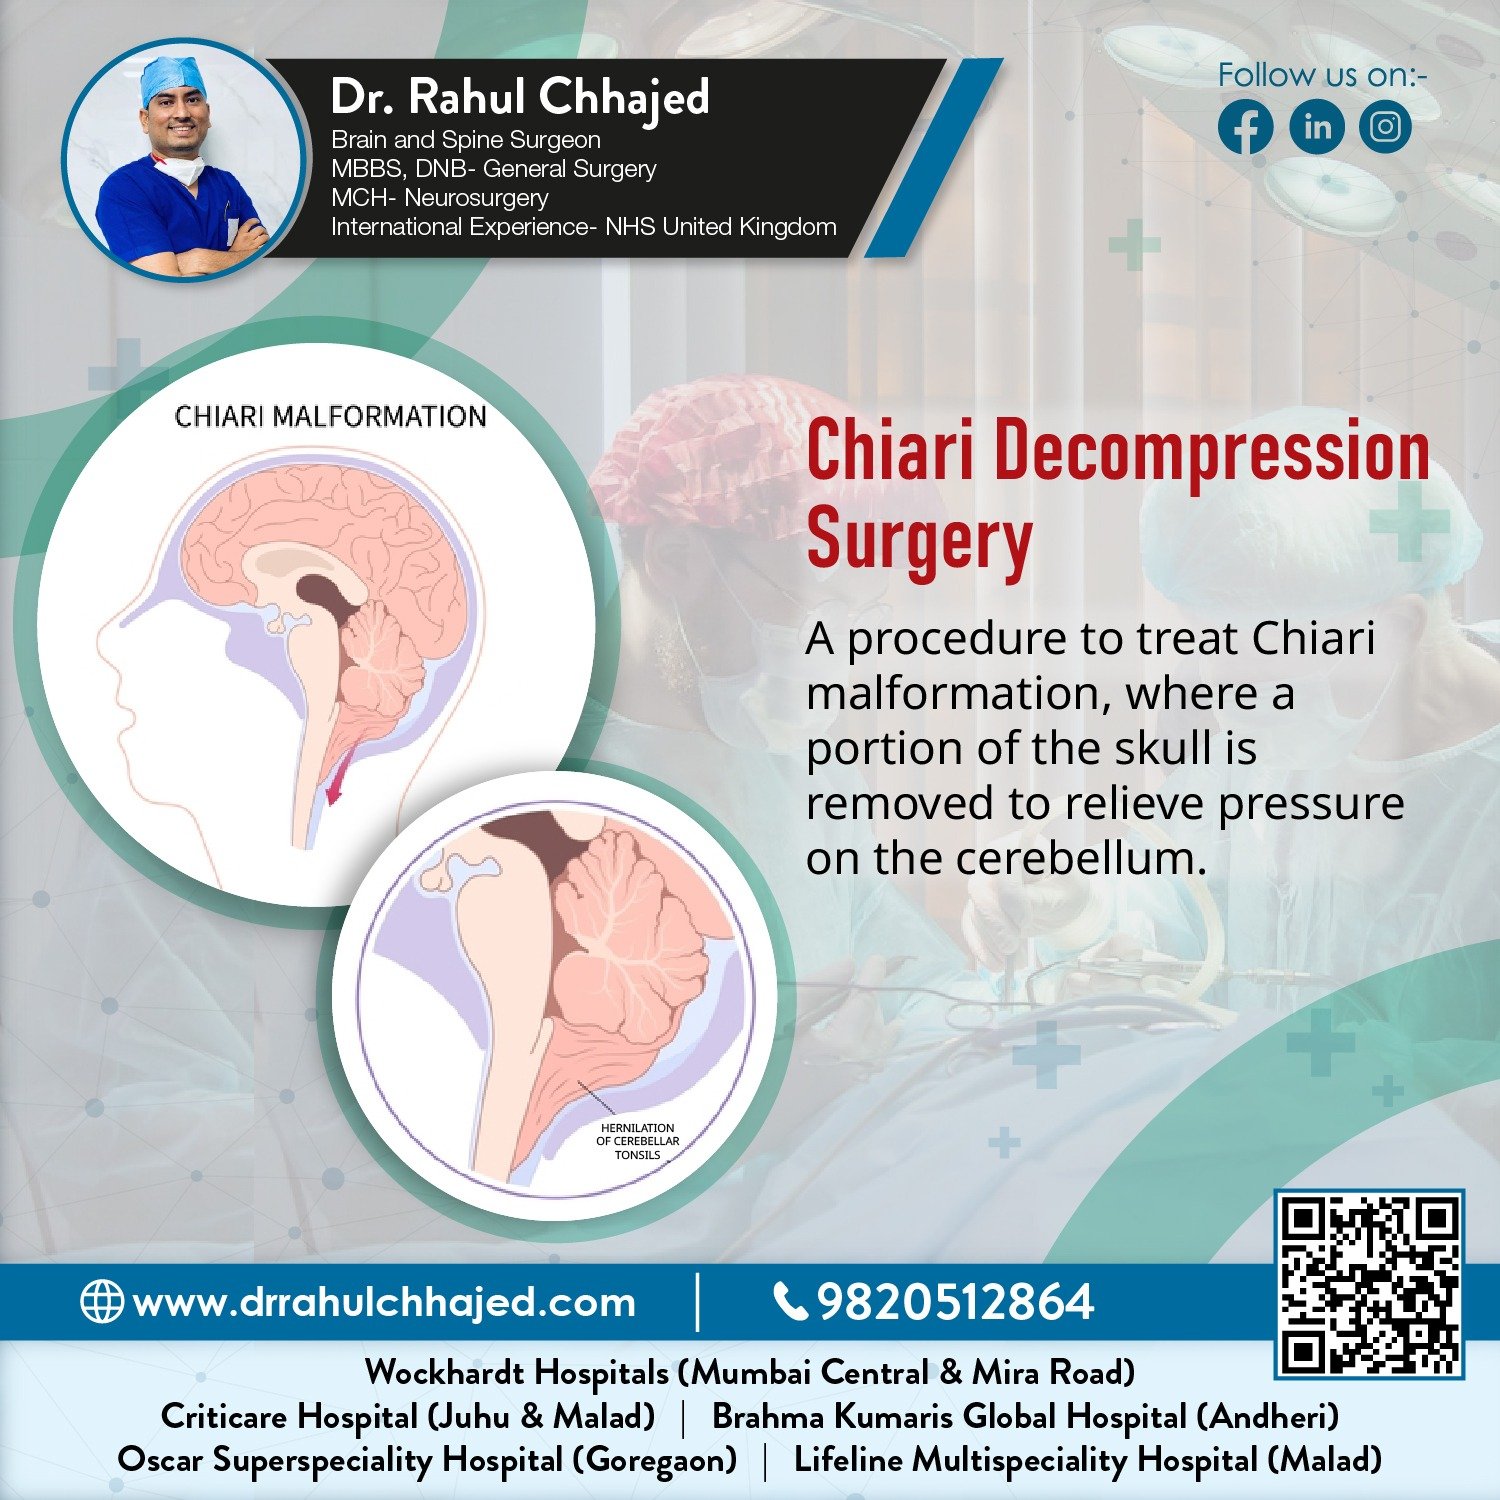

Spine Surgery

Dr. Rahul is a highly experienced spine surgeon specializing in diagnosing and treating spinal conditions. He performs a wide range of surgical options for spinal conditions, including minimally invasive techniques, spinal fusion, and disc replacement.